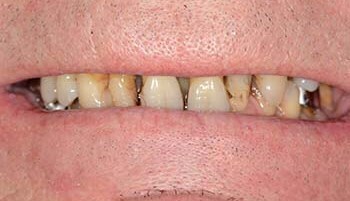

Ce patient de 62 ans présente deux grands bridges maxillaires. Celui de droite présente trois défauts : deux piliers (17 et 11) sont perdus et l’esthétique des racines des dents antérieures est peu satisfaisante.

Les racines des dents antérieures son très brunes du fait de l’ancienneté de leur dévitalisation.